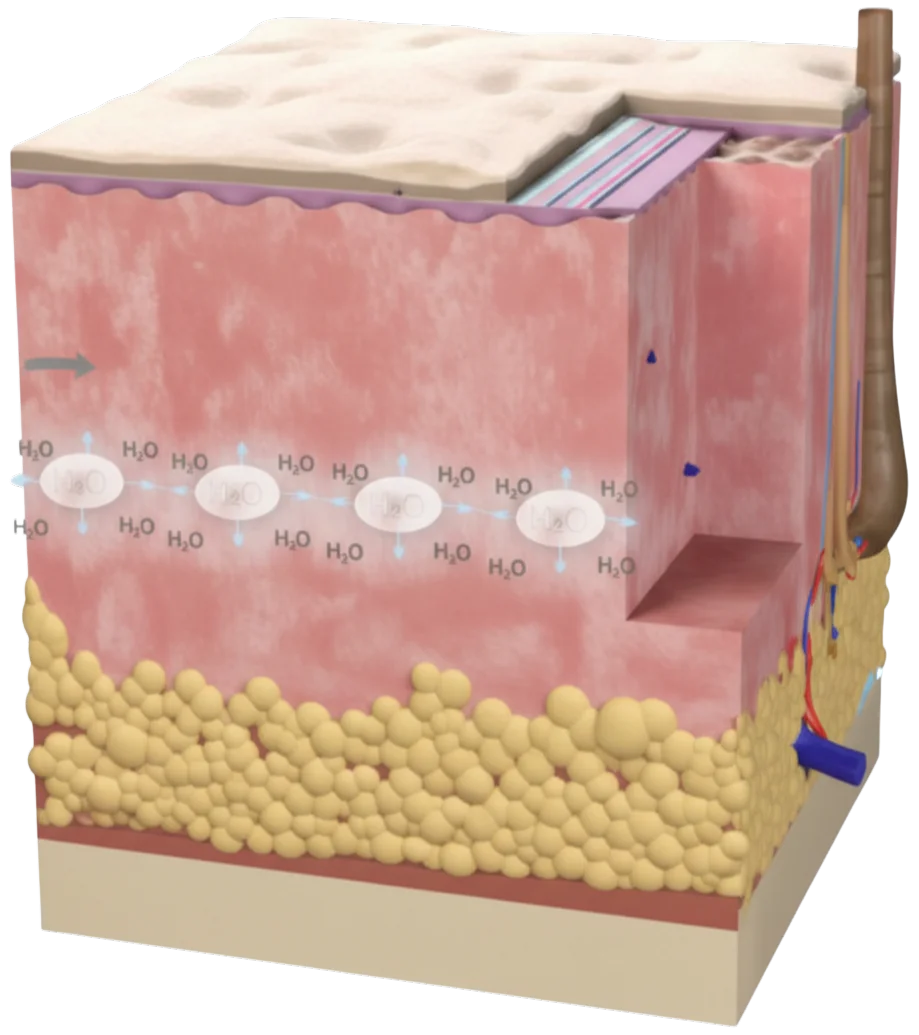

- ALL IN DERM skin booster by Neo Areum is an anti-aging product for improving skin aging and skin quality.

- It is a complex anti-aging solution that contains a total of 67 complex ingredients (Glutathione, PDRN, HA and Peptides)

- Stimulates fibroblast

- Increases collagen

- Neutralizes free radical

Skin appears dry and dull

Skin booster is manually injected into the skin

Well hydrated skin appears plumper and more radiant